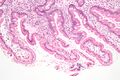

Duodenum with brush border (microvillus)